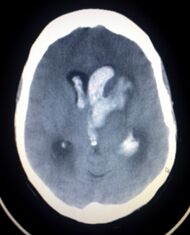

CT scan of a spontaneous intracranial hemorrhage | |

يعتمد بصفة رئيسة على تصوير الدماغ، ومن أكثر طرق التصوير استعمالاً التصوير الطبقي المحوري (الشكل 3)، وبدرجة أقل المرنان المغنطيسي. وجدير بالذكر أن تصوير الدماغ قد يخفق في إظهار النزف في نحو 5% من المرضى، وفي هذه الحالة يمكن اللجوء إلى استقصاء آخر هو البزل القطني للسائل الدماغي الشوكي. وتظهر دراسة السائل وجود أعداد كبيرة من الكريات الحمر، مما يثبت حدوث النزف.